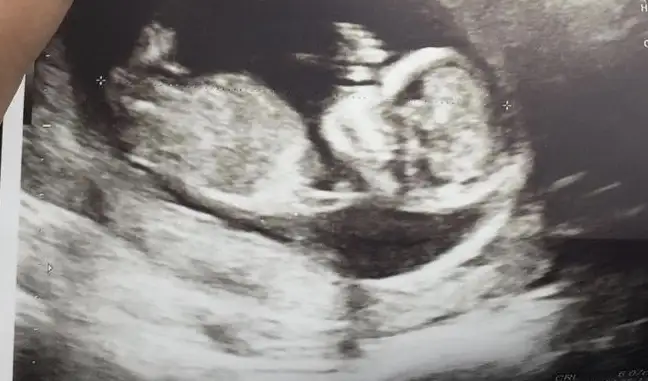

👫 11 yada 12 yada 13 hafta Nub usg nizi konumuza paylaşın

Arkadaşlar tahmin var mı? Özellikle ikra meyra :) Rabbim hayırlısını nasip etsin inşallah. 11+5

Evet oda kıza benzetti :) yanılma ihtimalimiz yüksek bu haftalarda ama kıza benzettim dedi! ama 3 hafta sonra falan gel artık şimdilik sıkı takibe gerek yok, hastalık falanda var diye.

İkimizde kız demişiz bencede kızdır 😍